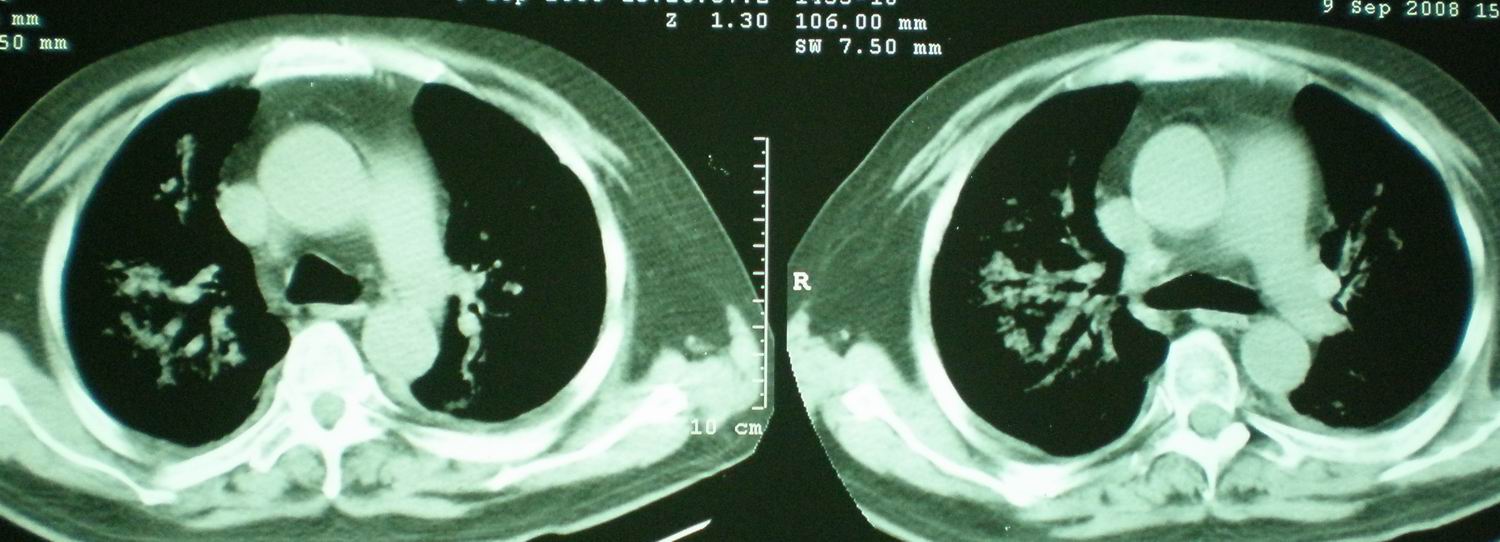

2008年9月8日ct片:

急性心衰所致肺水肿,双侧胸腔积液,少量心包积液可能?结合临床及其它检查.

我仔细看了下病人的出院小结,当时情况危急,诊断里有1型呼衰。心包周围的是脂肪密度。结合三次ct扫描的图象分析,个人认为:1、病人目前肺部病灶基本消失,双侧胸腔内少量积液,抗结核治疗才一个多月,就算是结核,抗结核治疗有效果,为何效果如此好,一点纤维灶的痕迹都没有呢,再就是患者做过气管镜检查及活检、痰检均未找到结核的证据。所以不支持结核的诊断。

2、结合现在的ct片,考虑:肺水肿及真菌感染,双侧胸腔积液。

急性呼吸窘迫综合征,肺水肿,与激素减量太快有关.双侧胸腔积液.

机遇性感染。双肺实质满布。且以肺门周围为主。不象结核。